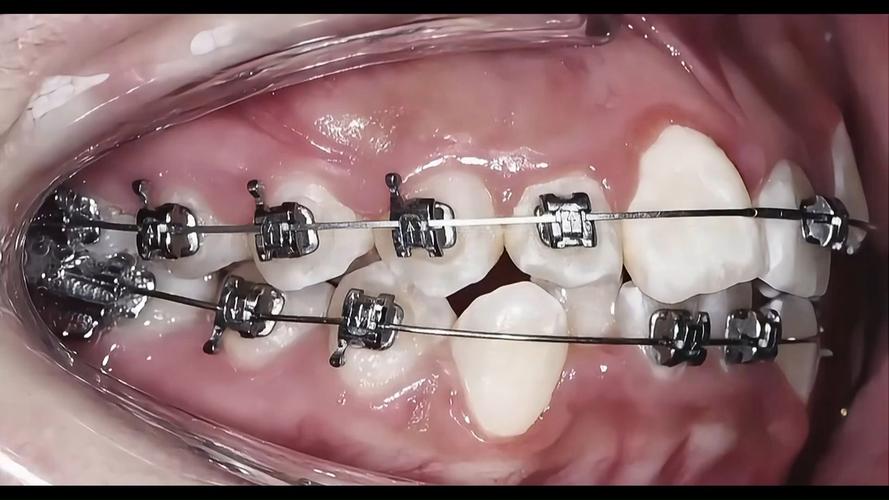

| 传统固定矫正 | 矫正力稳定、性价比高、适用范围广(复杂病例) | 美观度差、口腔清洁难度大、舒适度较低 | 各年龄段闭锁合患者,尤其需拔牙或颌骨调整者 |

| 自锁托槽矫正 | 摩擦力小、矫正效率高(复诊间隔延长4-6周) | 价格较高、托槽体积较大可能影响舒适度 | 对复诊时间有要求、追求高效矫正的患者 |